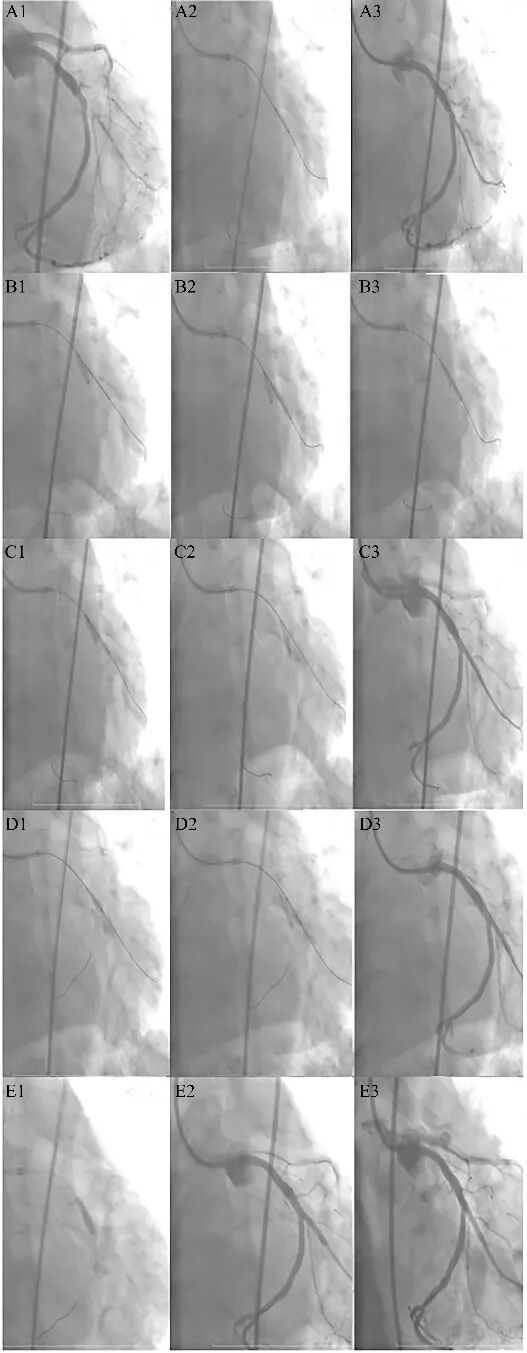

OSDOKINA术式的应用案例(图6)

图6 OSDOKINA CRUSH技术处理钝缘支开口病变[1]。

1、预处理(A):第二钝缘支(OM2)开口狭窄 98%(A1),2.5 × 12 mm 球囊预扩张(A2),预处理充分(A3)。

2、释放支架(B):回旋支3.5 × 12 mm非顺应性球囊12 atm扩张(B1),然后OM2内支架回撤至开口对回旋支球囊产生压痕,支架以12 atm释放(B2),稍回撤支架球囊以16 atm对近半段支架进行塑形(B3)。

3、第一次对吻(C):分支支架球囊和主支球囊以12 atm完成第一次球囊对吻(C1)。撤离分支支架球囊,主支球囊14 atm对OM2支架开口进行挤压(nano-crush)(C2)。

4、第二次对吻(D): OM2支架进行重置导丝,然后分阶段对吻:OM2采用2.75 × 15 mm非顺应性球囊 18 atm后扩张(D1),然后主支采用3.5 × 12 mm 非顺应性球囊12 atm扩张,最后12atm完场第二次对吻(D2),造影未见明显夹层(D3)。

5、主支药球(E):主支采用4.0 × 16 mm药物球囊14 atm *90秒扩张,防止再狭窄(E1)。造影检查主支无夹层和血栓形成(E2-E3)。